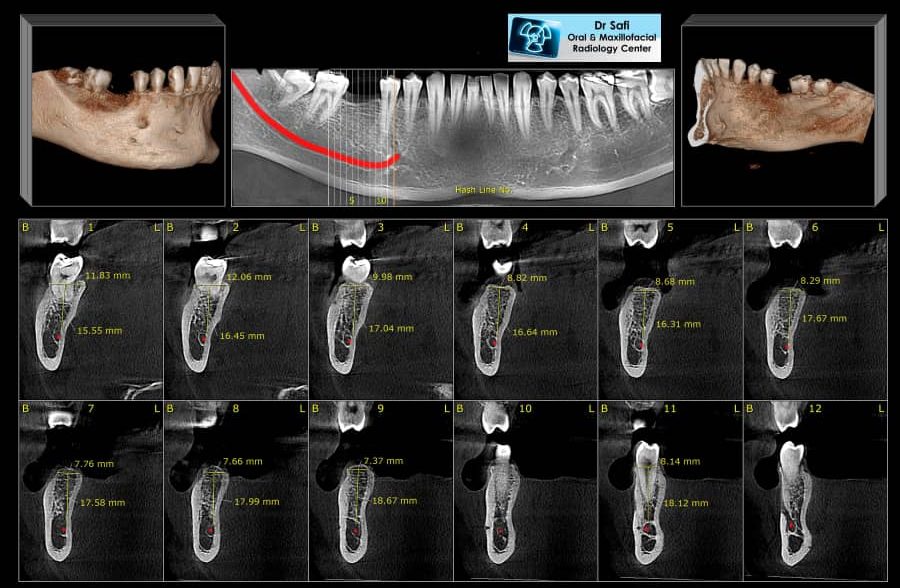

رادیوگرافی (CBCT)

CBCT-02